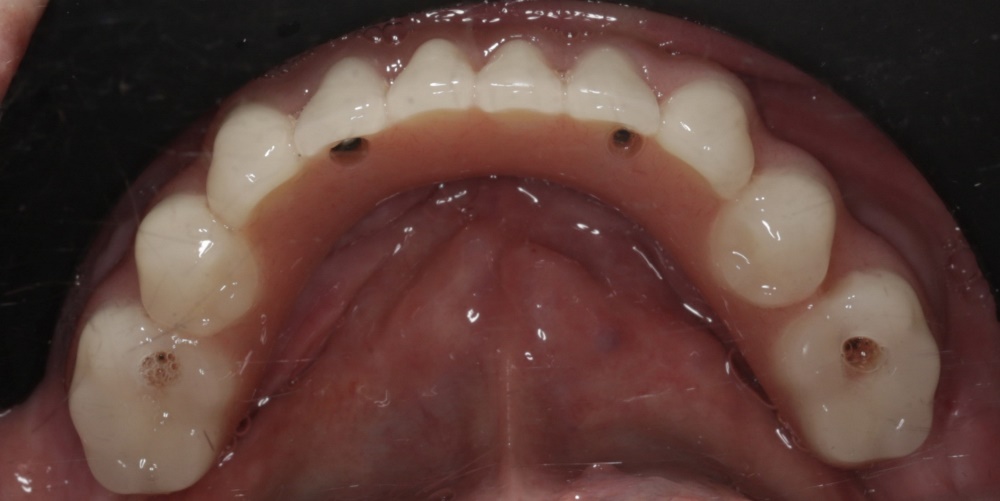

Имплантация жевательных зубов,

это самая востребованная операция.

рентген имплантатоы

фото коронок